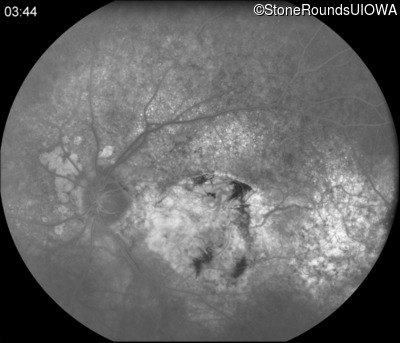

Fluorescein Angiography - Left - 20/125

Exemplar